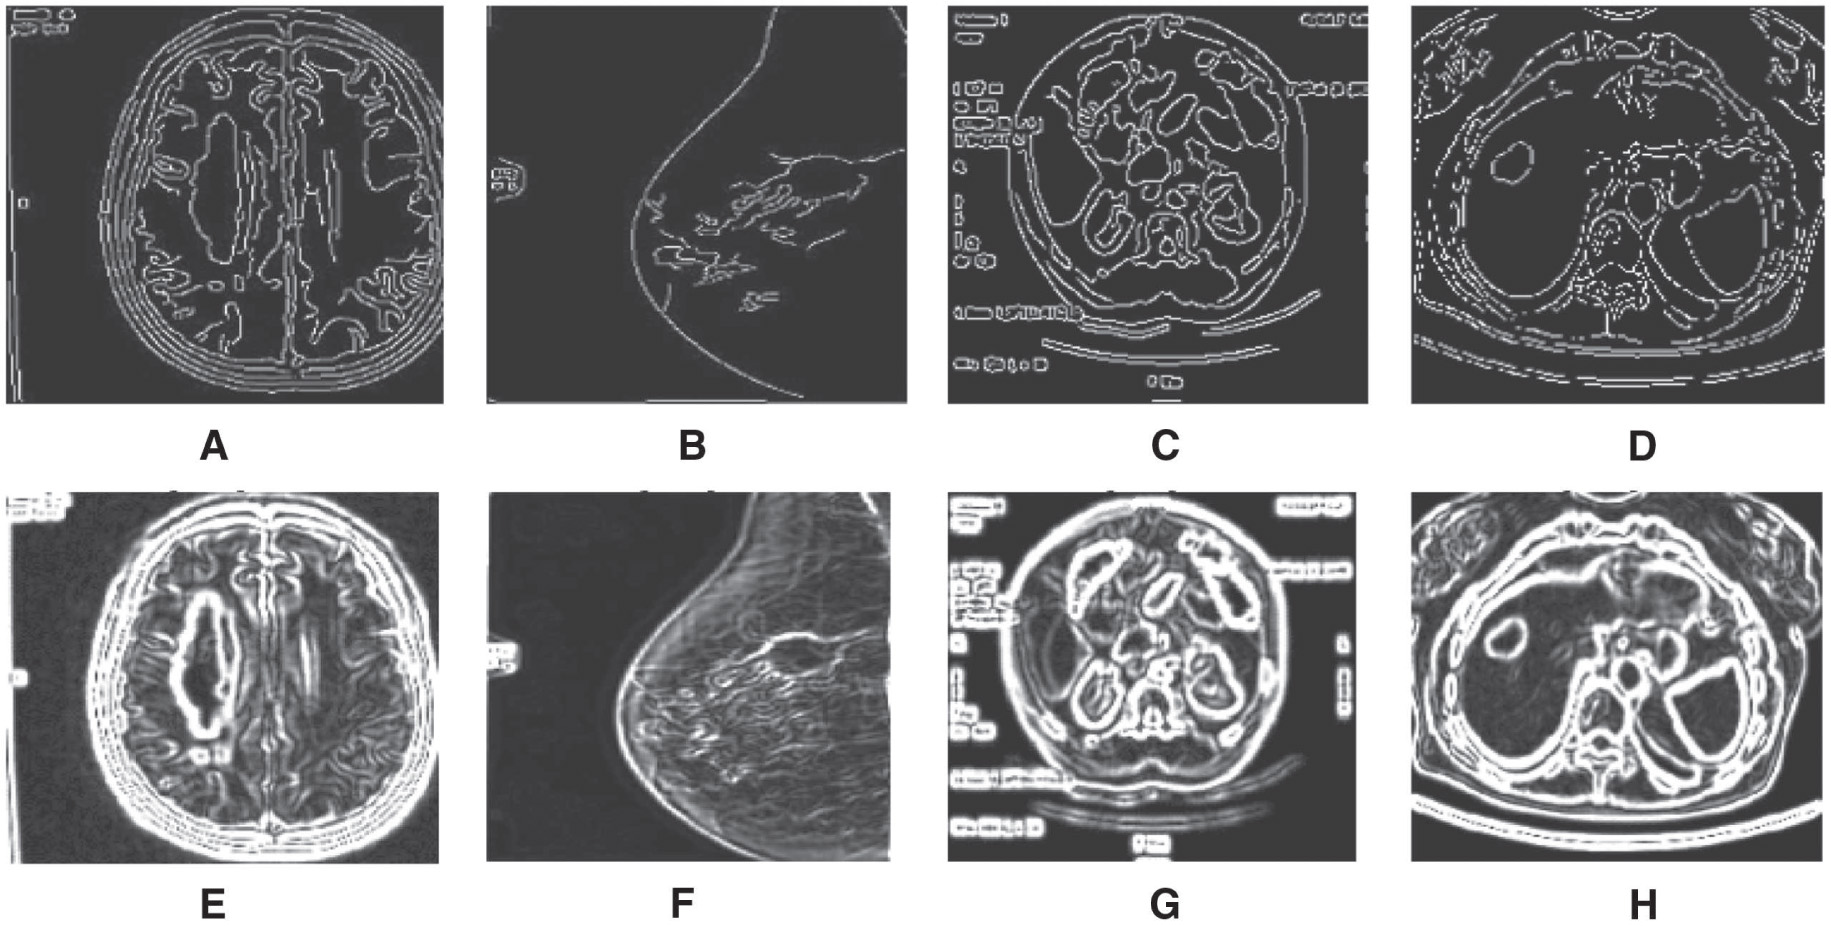

The results of region growing algorithm with manual seed point selection are depicted in Figure 3, and (x, y) represents seed point for the region growing technique. The threshold value of T = 0.2 is chosen for all the inputs, and the seed point coordinates will be a changing parameter, and it depends on the region of interest. The region growing process terminates when the intensity difference between the region mean and new pixel becomes greater than the threshold. Out of the conventional edge detectors, Canny algorithm generates efficient results. The Canny edge detection algorithm results are depicted in Figure 4. The Gauss gradient edge detector results are depicted here, and the parameter sigma plays a crucial role. For all the input images, sigma = 1.5 was chosen [43]. Boundary extraction is better in Gauss gradient edge detector technique. The gradient-based watershed algorithm results are depicted in Figure 5. Here, prior to segmentation, pre-processing was done by the median filter of kernel size 3 × 3.

Edge Detection Algorithms for Boundary Detection in Medical Images; (A–D) Canny Edge Detector Output, (E–H) Gauss Gradient Edge Detector Output.